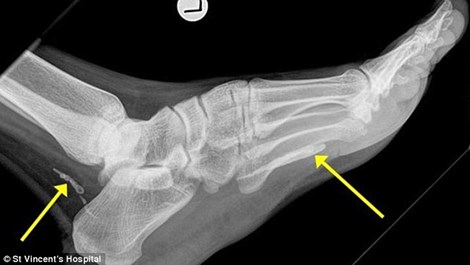

Người đàn ông này đã đến Úc vào 4 năm trước, gần đây anh ta tới gặp bác sỹ để khám bàn chân do nó sưng phù mãi không hết suốt 1 năm. Tiến sỹ, bác sỹ chuyên về bệnh truyền nhiễm Jonathan Darby đã thấy trong phim X quang 2 mảnh của con “giun Guinea” cuộn tròn trong phần mắt cá và bàn chân người đàn ông. Sinh vật này có thể đã chết vì ... già và bắt đầu phân hủy trong cơ thể anh ta.

Ảnh chụp X quang cho thấy những phần còn lại của con giun